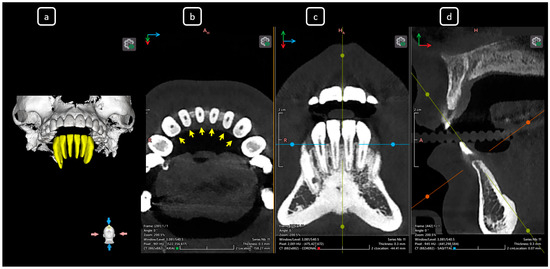

Cone beam computed tomography (CBCT) is a valuable diagnostic tool for evaluating the upper airway and maxillofacial region. This report demonstrates the clinical value of CBCT in identifying significant anatomical variations in endodontics, incidentally detected on a non-endodontic CBCT scan. A 23-year-old female patient underwent CBCT imaging at the Faculty of Dentistry-UJED to evaluate her upper airway. CBCT imaging revealed a unique, complex, and unusual anatomy of mandibular root canals, characterized by Vertucci’s type III root canals in the anterior sextant and co-occurrence of bilateral C-shaped mandibular second molars (type C2 according to Fan’s classification). No therapeutic interventions were initiated due to the patient’s asymptomatic status. CBCT imaging is a valuable tool for integrated diagnostic approaches, underscoring its role in thorough patient management. The integration of multidisciplinary interpretation of CBCT data can enhance diagnostic accuracy and optimize patient records and management, emphasizing the importance of collaborative efforts between radiologists, clinicians, and endodontists. Documenting and sharing such findings can increase awareness of rare anatomical variations, facilitating detection and contributing to medical knowledge. Full article

Figure 1